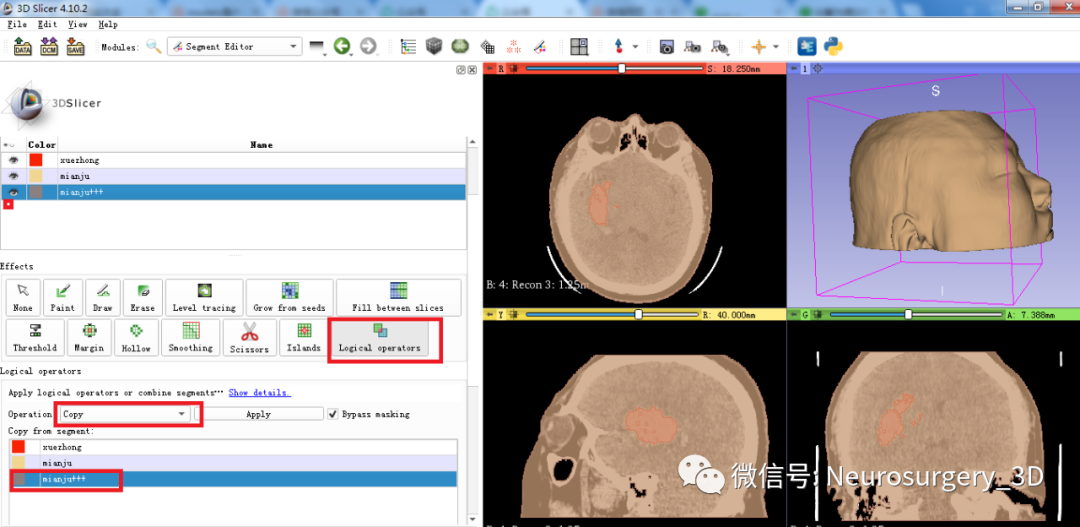

二)利用Logical operators逻辑运算模块的复制、相减功能生成面具模型

3、利用Logical operators逻辑运算模块复制头颅原始模型并扩大。

4、再次利用Logical operators逻辑运算模块,运算后重建出面具三维模型

运算后结果